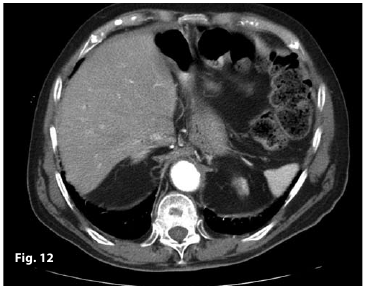

Figure2

Figure12